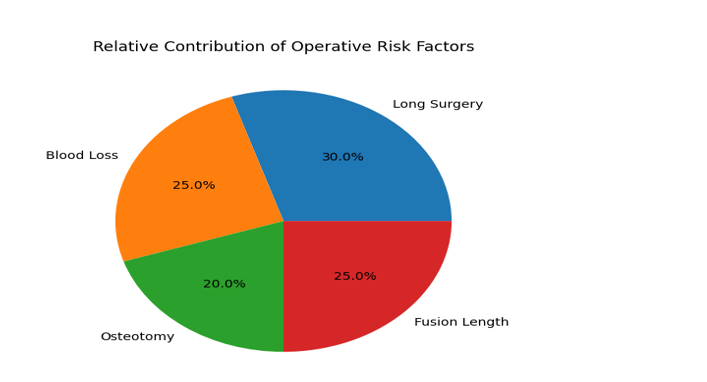

Neurovascular Outcomes in Adults Undergoing Surgery for Spinal Deformities: A Narrative Review

Background: Neuromuscular spinal deformities in adults are increasingly recognized due to improved survival among individuals with chronic neurological and neuromuscular...Read More